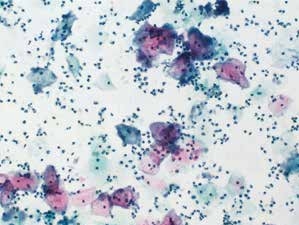

图2-3 细菌性阴道病(中倍、液基、巴氏染色)

多量线索细胞和炎细胞,球菌和线索细胞是细菌性阴道病的主要细胞学表现。

细菌性阴道病是最常见的妇科感染,主要由于乳酸杆菌缺乏导致阴道pH值增加,使其他球菌或杆菌得以生长。朦胧的背景,小的球状杆菌,鳞状细胞表面覆盖着许多细菌,主要为球菌,嗜碱性,使细胞表面和细胞轮廓模糊不清,像有薄膜覆盖,这种特殊形态的细胞称为线索细胞(clue cells)。显微镜下查见线索细胞,报告菌群失调,提示细菌性阴道病。